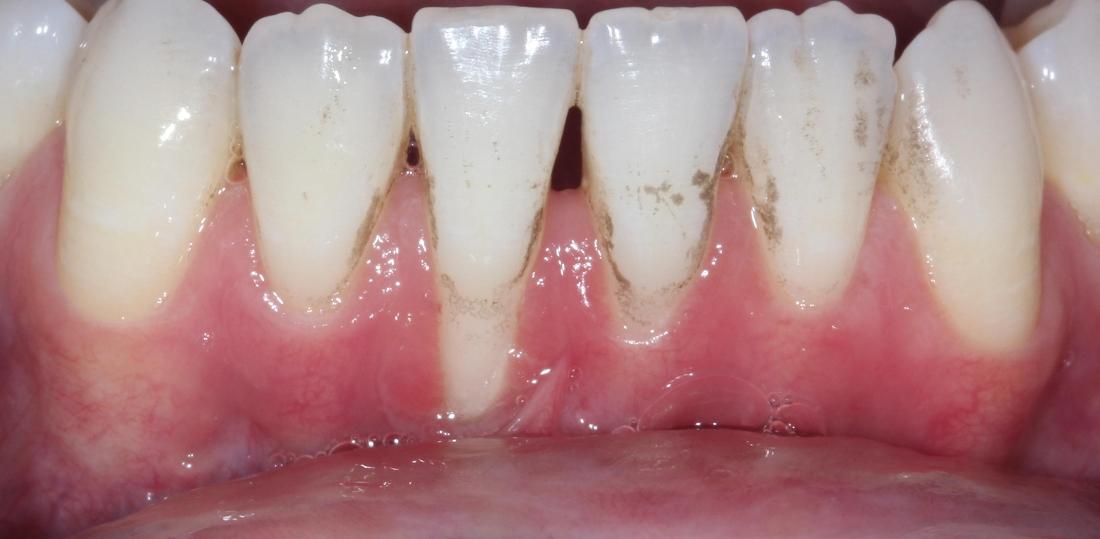

After: 3 months after gum grafting